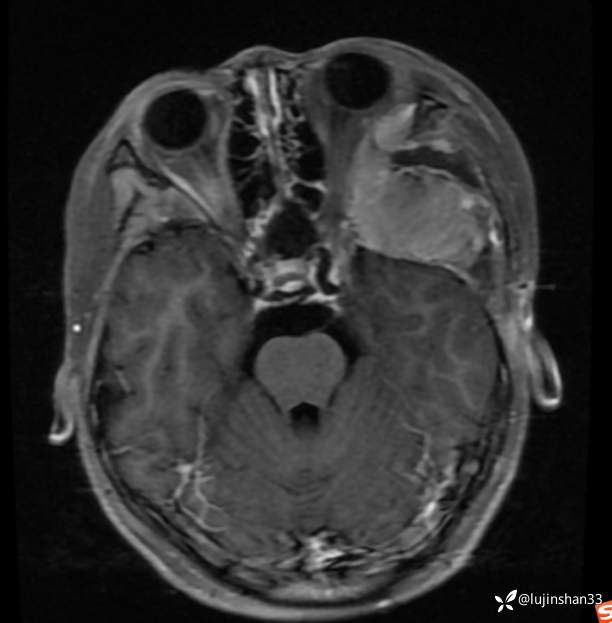

简要病史:患儿父母半年前发现患儿左颞部较右侧突起,无伴随症状,未重视未诊治,1月前,患儿左颞部肿物长大,伴头晕,向一侧倾倒感,头痛,两次剧痛,余为胀痛,偶有夜间出现左下颌区域皮肤麻木,咀嚼时左面部疼痛,10天前,患儿出现左眼睑肿胀伴疼痛,睁眼疼痛加重,不伴视力障碍,无畏寒发热,无意识障碍,无饮水呛咳,在XX同仁医院行颅脑核磁示:左侧颞下窝占位。门诊以“颞下窝占位(左)”收入院。患者目前精神状态良好,体力正常,食欲正常,睡眠正常,体重无明显变化,大便正常,排尿正常。

临床诊断:颅中窝、颞下窝小圆细胞恶性肿瘤

治疗经过:颅中窝入路侧颅底、颞下窝肿瘤切除、腹部脂肪取出、术腔填塞术

2021年8月复查MRI